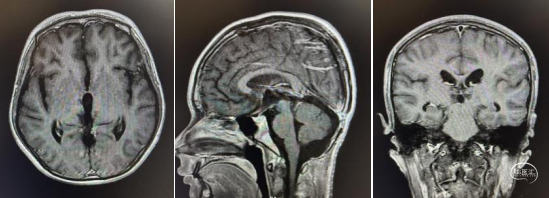

头部MRI显示:松果体区可见一形态不规则肿块,大小约52mm*50mm*51mm,其内信号混杂,呈短-长T1,短-稍长-长T2信号,增强后实质部分可见明显不均匀强化。肿瘤部分突入三脑室内,与三脑室左侧壁及左侧丘脑分界不清,中脑导水管受压变窄,三脑室及侧脑室扩张。右侧脑室前角可见一引流管影。

术前MRI